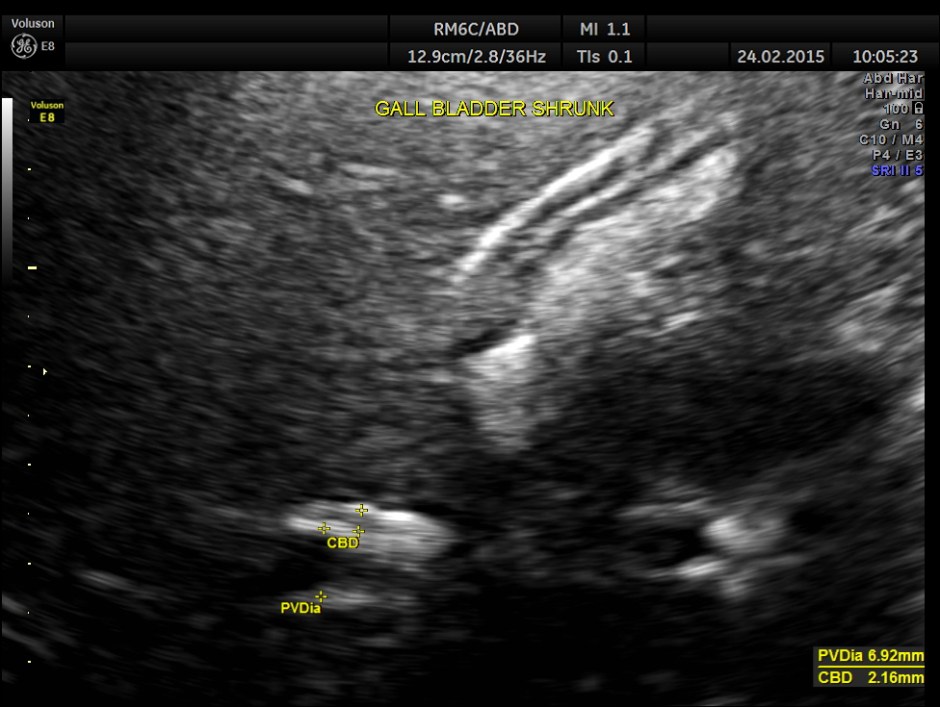

This was a 23 year old young lady , who was evaluated elsewhere for menstrual irregularities . She was reported to have a gallstone . She had no digestive complaints. She went for a 2nd and 3rd opinions, where the gallstone was not seen.She also underwent a CT scan , which reported a shrunk gall bladder and gallstone was not seen. She came to me for another opinion. She was in an over night fasting status ( almost 14 hours after her last meal or drink ).

The following is what was seen.

Completely collapsed and shrunk gall bladder in spite of over night fasting.